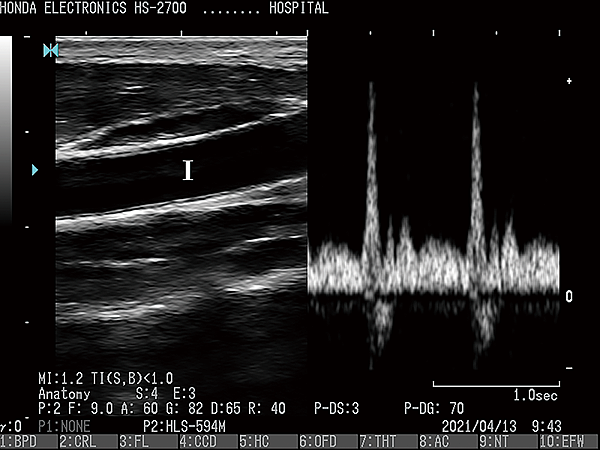

HS-2700支持CFM(彩色血流向)和PD(功率杜普勒)模式。

它們將適應廣泛的醫療應用。